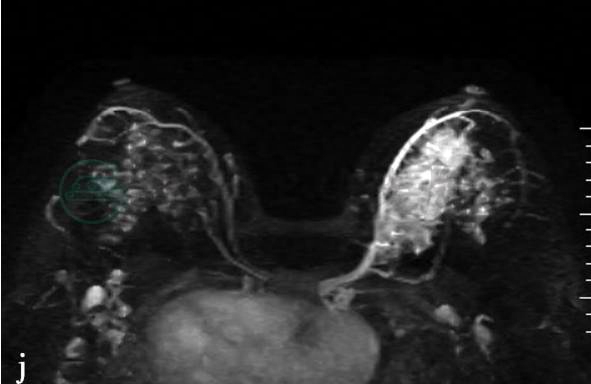

(2)病例2:

MRI平扫及增强扫描。

图2 图2f~h,分别为MRI动态增强前及增强后1min、8min。图2i,病变时间-信号强度曲线图。图2j,MIP图示病变侧血管较对侧明显增粗、增多,皮肤未见明显异常,腋下未见肿大淋巴结。图2g、h,分别为动态增强MRI示左乳中上方片状不均匀强化,整体呈段性分布。图2I,病变区时间-信号强度曲线呈平台型,范围约5.0cm×3.3cm